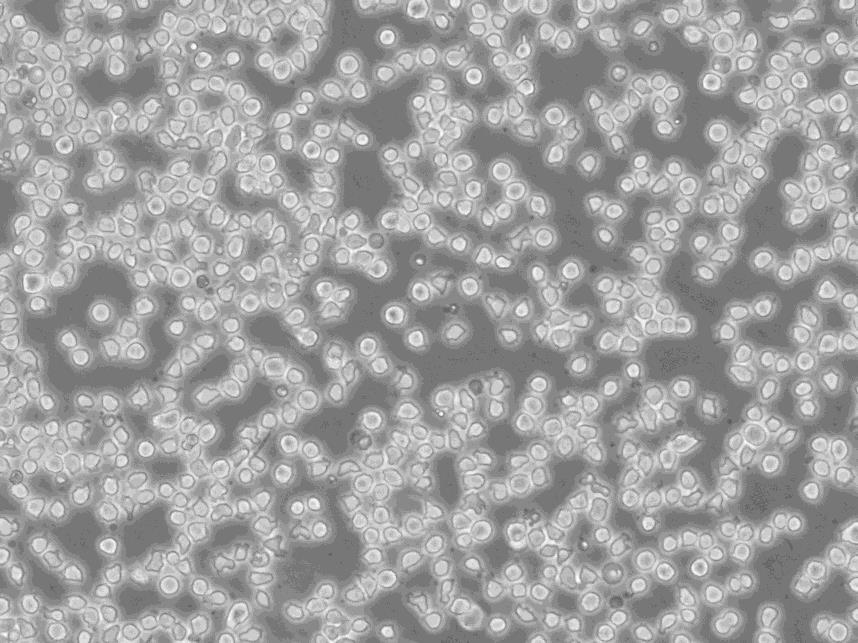

细胞形态:淋巴母细胞样

细胞生长:悬浮

细胞生长特性:悬浮生长

细胞形态特性:淋巴母细胞